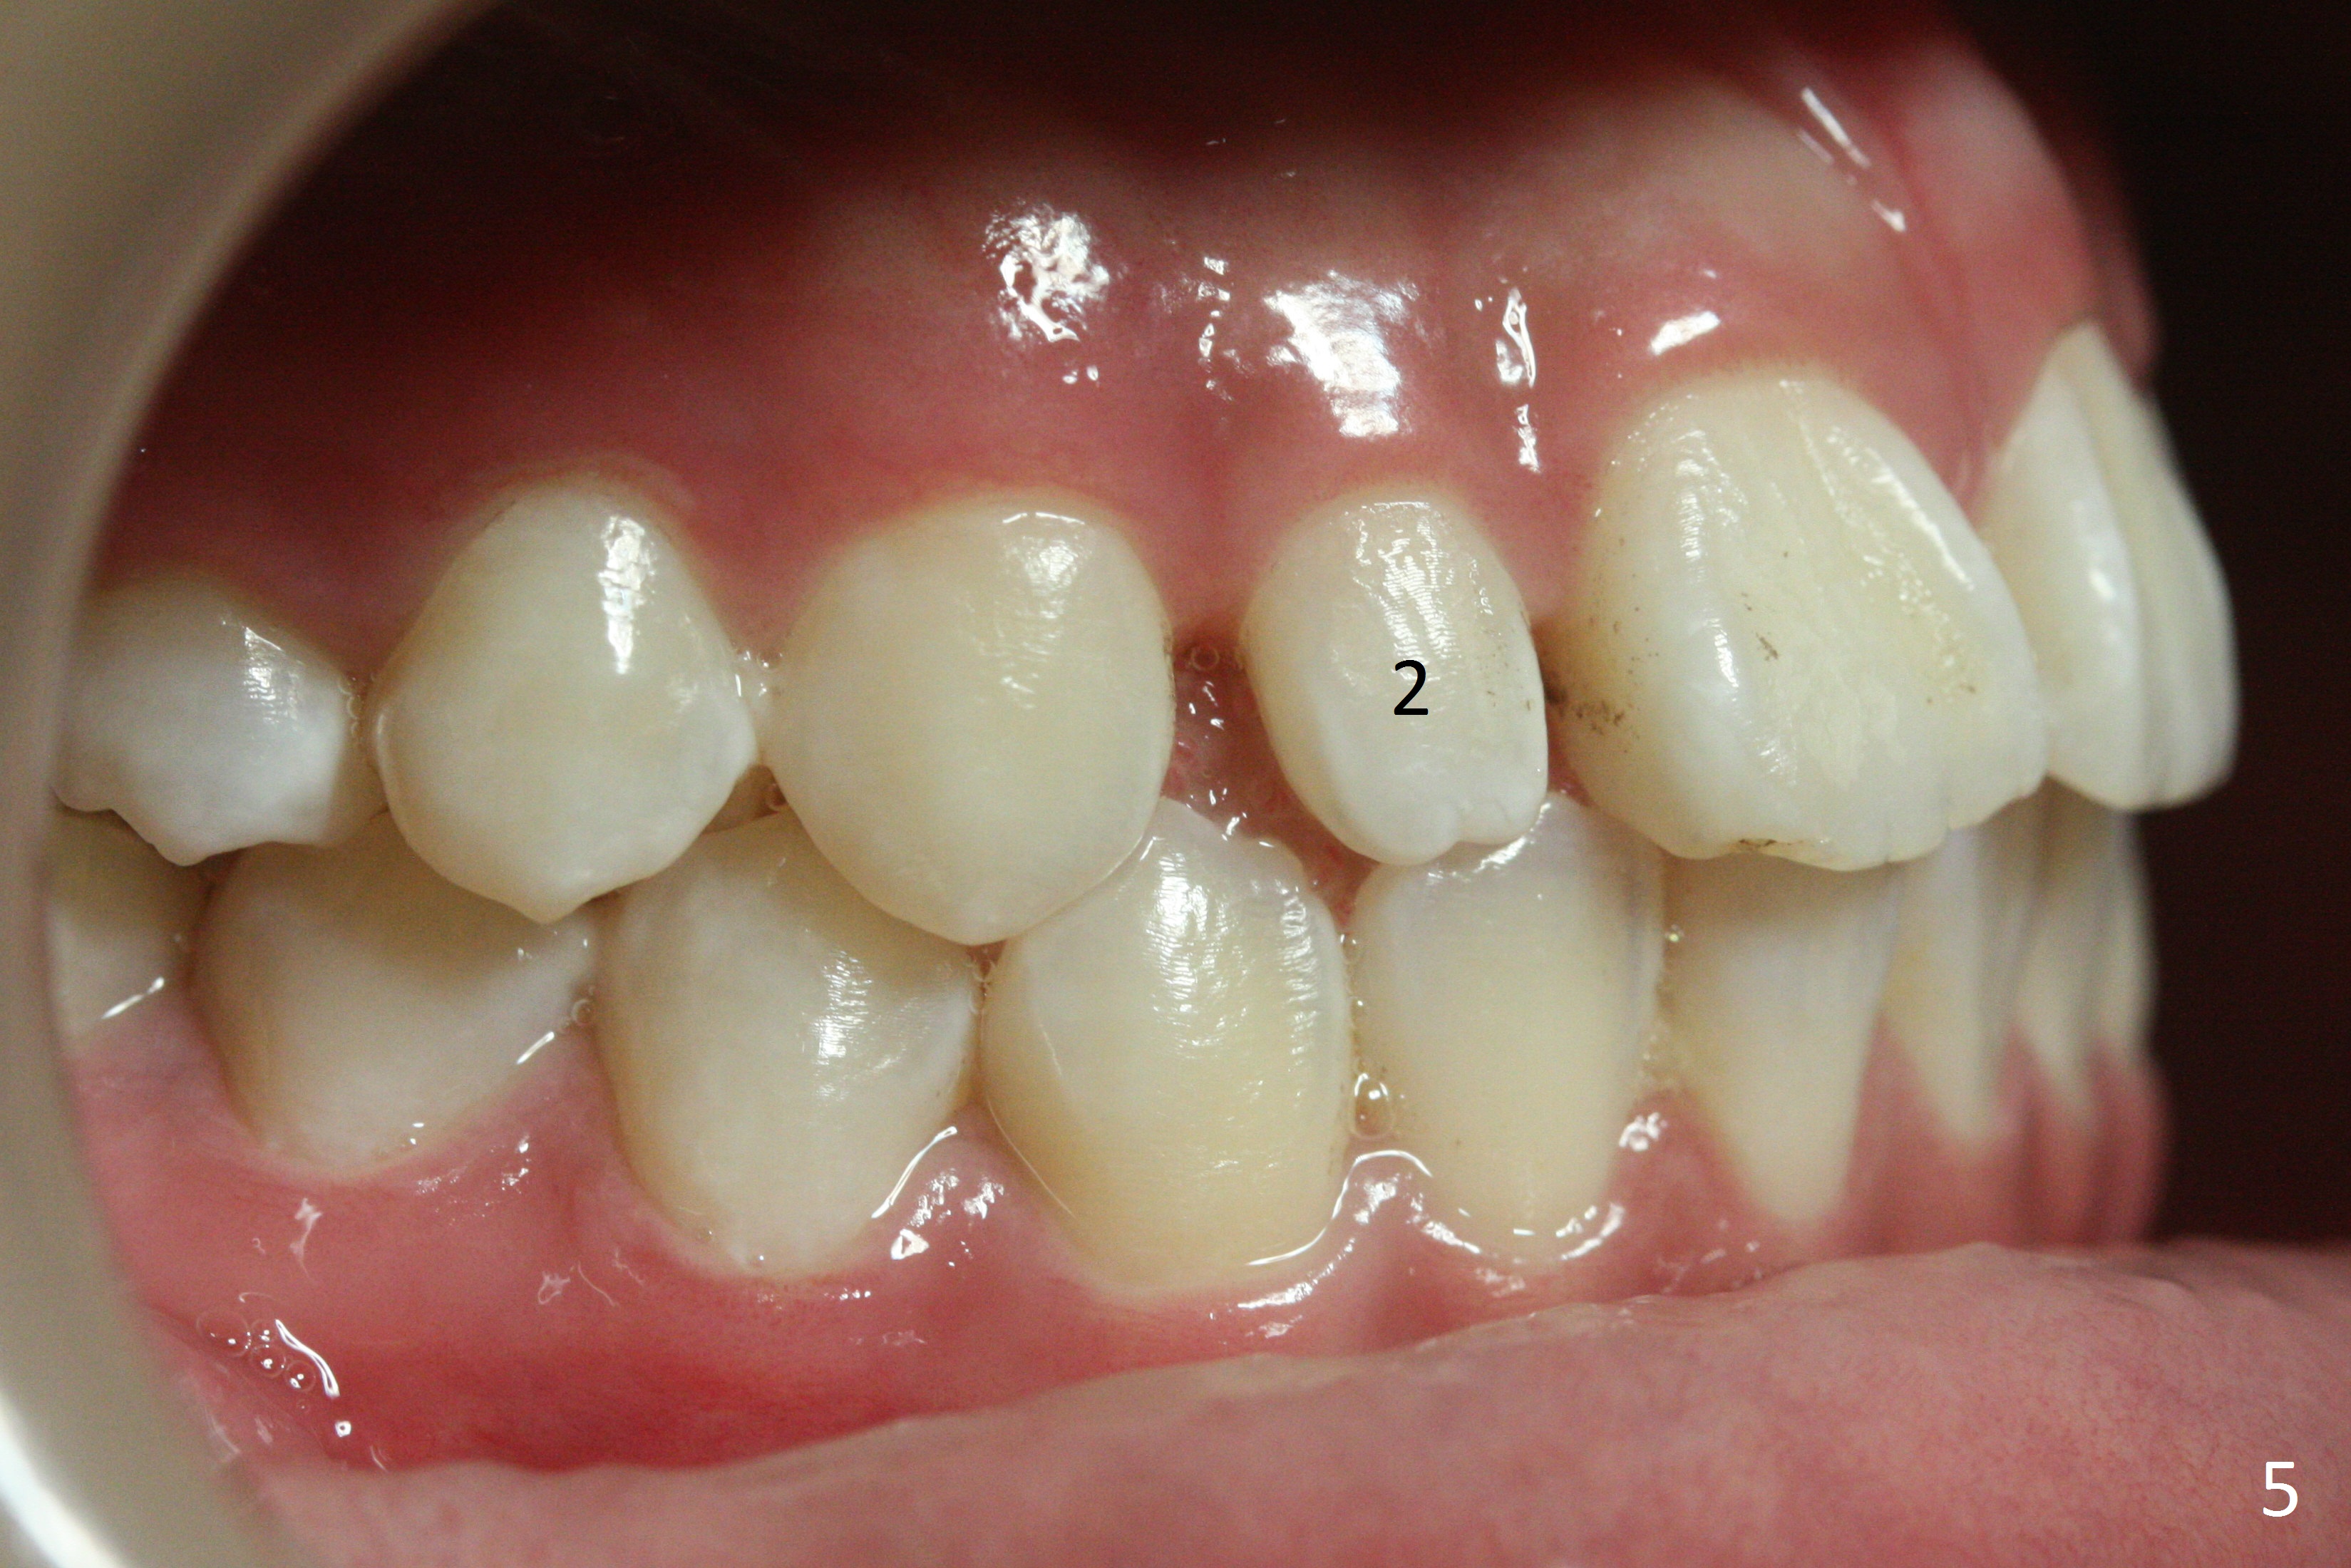

Two sisters (Sophia, 13 years old and Selina, 11) present to clinic for orthodontic treatment. Dental anomalies of Sophia include microdontia of the upper lateral incisors and congenital missing of the upper right permanent canine (Fig.5,6). For Selina, the upper right lateral incisor (Fig.5') and the upper left second bicuspid (Fig,6') are in cross bite.